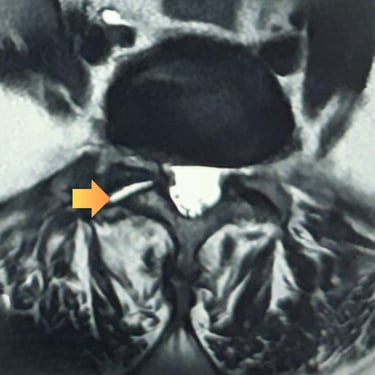

La listesis lumbar L5–S1 es una afección en la que una vértebra se desliza sobre otra, provocando inestabilidad, dolor lumbar y, en muchos casos, compresión de las raíces nerviosas. Cuando el tratamiento conservador no logra controlar los síntomas, la fusión intersomática transforaminal (TLIF) se presenta como una opción quirúrgica efectiva. Este procedimiento permite descomprimir las estructuras nerviosas, restaurar la alineación vertebral y lograr una fijación sólida mediante tornillos transpediculares e injerto óseo. La técnica TLIF reduce el dolor, mejora la estabilidad de la columna y favorece una recuperación funcional progresiva y segura.